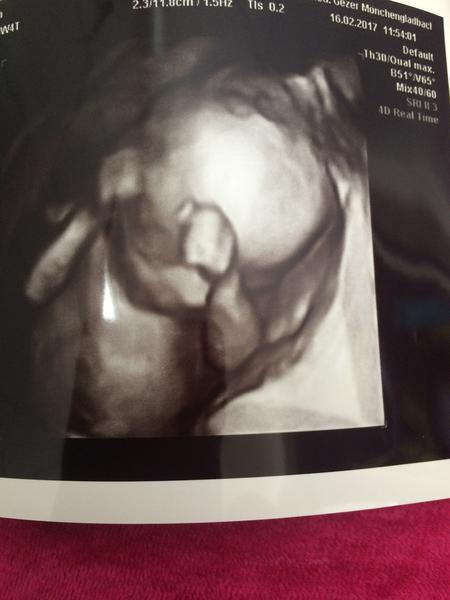

Ahojte 🙂 taak nastastie vsetko v poriadku 😉 malinke rastie ako z vody 😇 pani doktorka nam ukazala tvaricku srdiecko skontrolovala aj chrbatik nozicky 🙂 este aj celu dlan bolo vidno aj take malinke chodidielko 😍 aaa konecne vieme co to zblnkoce v brusku 🙂 mame chlapceka 😍 ❤ mame aj fotecku 'ruka hore' 😀 😀 😍

Podľa pani doktorky má moje bábätko ukazkovu citujem "šušku" 😀 takže máme sa pripraviť na 1000% dievčatko. Veľmi sa tešíme. Termín 7.7.2017. pridávam fotecku tej mojej herečky.